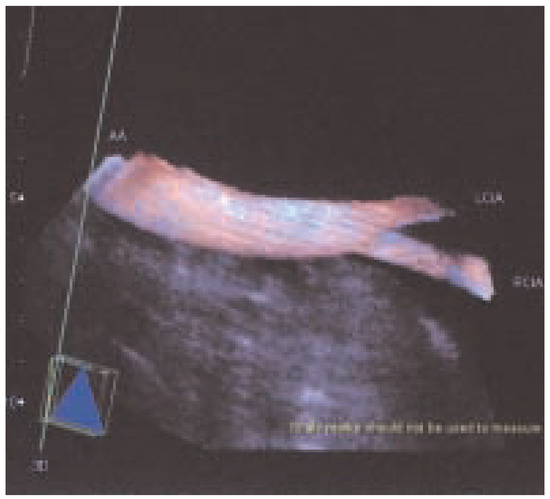

Dreidimensionale Angiosonographie

by Michel Zuber

Viele Gefässsysteme lassen... Full article

Show Figures

Figure 1